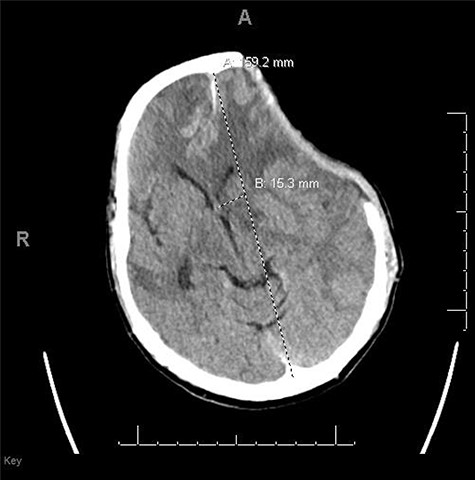

A 59-year-old male was found in the street with a head laceration. He was brought to the trauma bay as a pedestrian struck trauma patient with a prehospital GCS of 3. On arrival, his GCS was 11 (E3, V2, M6). An expanding neck hematoma was seen on exam. CT scan revealed scattered bilateral frontal contusions with hemorrhage in right basal ganglia, small bilateral acute SDH without significant mass effect, minimally displaced right temporal/occipital skull fracture and right-sided rib fractures 1–7 (flail chest) with hemopneumothorax (Fig. 1).

He was paralyzed, intubated and taken emergently to the OR due to nonresponsive hypovolemic shock. A right frontal ICP monitor was placed in the operating room while he was undergoing an emergency thoracotomy. Intraoperative ICP was in the 40s, and thus the patient was taken directly from the operating room to CT scan which showed enlargement of bilateral contusions, left greater than right, for which he was taken emergently to the operating room for a left hemicraniectomy (Figs 2 and 3).

CT head post thoracotomy with expansion of contusion with shift.